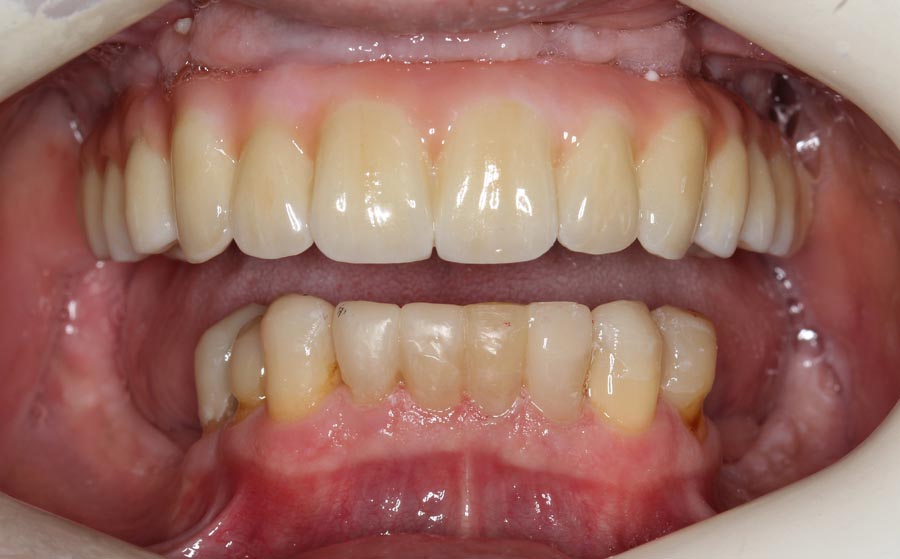

Smile of upper permanent and lower bonded teeth. The patient is starting to learn how to smile, again!

Final upper zirconium implant bridge. Final lower titanium/acrylic bridge. For patients with grinding habits, I recommend different materials in the opposing jaws to decrease the chances of breakage. Here, the lower acrylic teeth are softer than the upper zirconium which allows for tooth wear (attrition) instead of breakage.